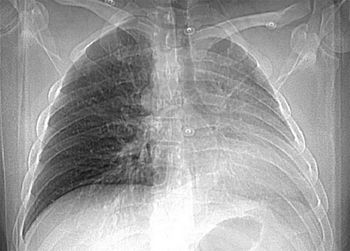

A 26-year-old man presented with sudden onset of palpitations and shortness of breath after incidentally taking tadalafil. He had no other symptoms and no history of illnesses during childhood. He drank socially but denied smoking and use of illicit drugs.